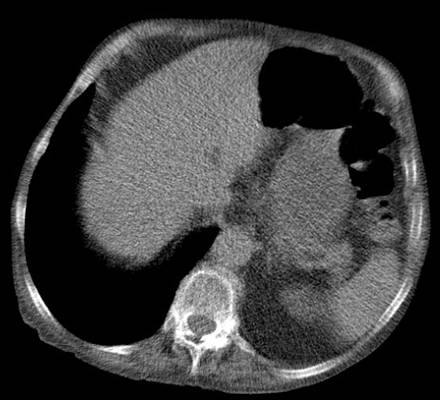

Thinner slice: higher noise

•Object ~ 5 mm

5mm